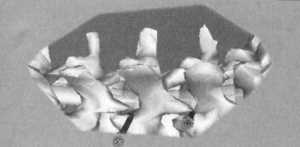

Рис. 7.1. |

На рис. 7.1 приведено начальное положение шурупов в общепринятых расчетных

точках. На рис. 7.2 с помощью симуляционной модели убраны контуры тела больного,

видны только ввинченные в тела позвонков 2 транспедикулярных шурупа расположенные

в классических расчетных точках. На рис. 7.3 с помощью симуляционной модели

убраны костные структуры. Визуализируется только розовый дуральный мешок, красные

диски и серые транспедикулярные шурупы. С этого угла зрения кажется, что положение

транспедикулярных шурупов идеальное. Однако на рис. 7.4 который представляет

собой рис. 7.3 повернутый в пространстве видно, что транспедикулярные шурупы

практически касаются края дурального мешка. Отсюда становится понятным, что

незначительное смещение медиально расположения входных точек или увеличение

наклона шурупа может привести к повреждению дурального мешка в случае если шуруп

внедрен через классическую расчетную точку. На рис. 7.5 шурупы введены с ошибкой,

один шуруп введен слишком медиально, другой - с углом наклона к средней линии

приближающимся к 50°. На рис. 7.6 после нивелирования контуров тела видно положение

этих шурупов. На рис. 7.7 убраны контуры кости и видно как оба шурупа повреждают

дуральный мешок.